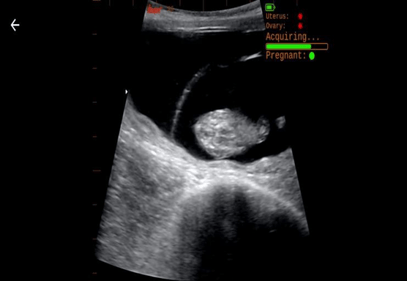

- While scanning, live image information is passed to the AI processor, and diagnostic information is displayed in the upper right corner of the image.

- As uterus and ovary structures are identified in the image, the corresponding indicators will change colors.

Uterus: Red <30%: Orange >= 30% <95%: Green >= 95%

Ovary: Red <30%: Orange >=30% <60%: Green >= 60%

- As identified structures are collected, the “acquiring” progress bar will fill. Once 20 valid images are collected, Herd IQ will begin to assess evidence of a pregnancy.

- If a pregnancy is detected, the progress bar will change to green and “Pregnant” will be displayed.

- If more images are collected that suggest the pregnancy is not valid, the progress bar will revert to red, and the pregnant indicator will change to red.